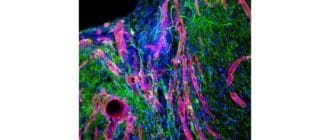

癌のための革新的な治療法を実験している科学者たちは、マウスの腫瘍をすでにうまく除去した標的注射を考案しました。 過去数年間に、すべてのタイプの癌に対してより効果的な治療法を研究する研究は、常に新しい希望を提供してきました […]

新しい研究論文は、脳卒中で損傷した脳組織の再増殖を助ける画期的な生体工学的ゲルを記述しています。 脳卒中は、脳の特定の部分への血液供給が有意に減少し、脳細胞死をもたらす場合に生じる。 脳卒中後、多くの人々は、過程で破壊さ […]